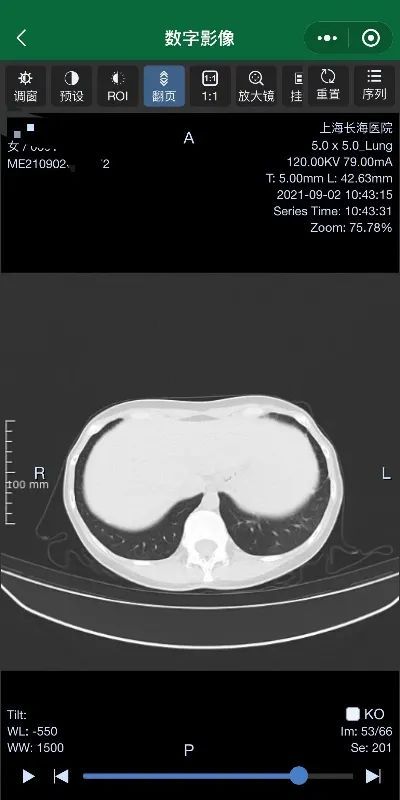

2.新增患者自助查询医学影像资料功能

方法一:通过微信小程序中“综合服务”—“影像查看”功能查看影像资料。

方法二:通过扫描纸质报告单中二维码扫码查看影像资料。